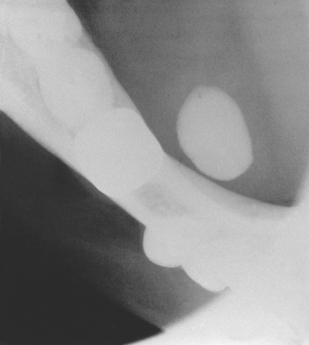

For parotid and submandibular tumours, CT scanning or MRI are the most helpful imaging techniques (Fig. 14.10). They will confirm that the mass being investigated is indeed intrinsic to the gland; they accurately image the borders of the tumour and show if it is well circumscribed (and likely to be benign) or diffuse and invasive (and likely to be malignant). In addition, scans show the relationship of the tumour to other anatomic structures and help with the planning of subsequent surgery. Unfortunately, in the case of parotid tumours, these scanning techniques cannot reliably image the facial nerve and therefore reliably determine whether the tumour is superficial or deep to the plane of the nerve. However, this plane can usually be inferred, as the course of the facial nerve is constant from the stylomastoid foramen, becoming more superficial and passing forwards over the masseter muscle.

image

Fig. 14.10 A large pleomorphic adenoma arising in the deep lobe of the parotid gland.